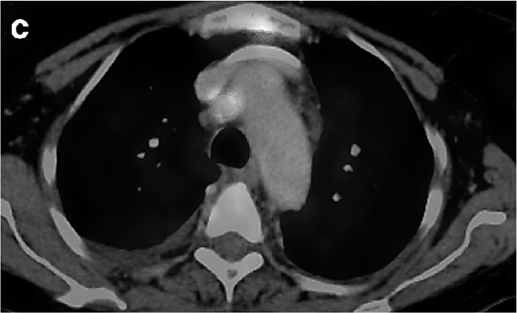

Um paciente de 62 anos de idade, tabagista ativo, cerca de 180 anos-maço, queixa-se de cansaço, tosse seca e perda de peso; por isso, procurou atendimento médico. O paciente referiu que pesava 100 kg e perdeu 10 kg. Realizou-se tomografia computadorizada de tórax, com evidência de lesão sólida de 2,1 cm em topografia de lobo inferior à direita, sólida, espiculada, com margens bem definidas e densidade de partes moles, assim como linfonodomegalia paratraqueal direita de 1,5 cm, paratraqueal esquerda de 1,2 cm e subcarinal de 2 cm. O paciente foi submetido a PET-CT de corpo inteiro, com evidência de hipercaptação de radiofármaco pela lesão (SUV 12) e pelo linfonodo representado na figura 2 a seguir.

Figura 1: TC de tórax sem contraste

Figura 2: PET-CT do tórax.